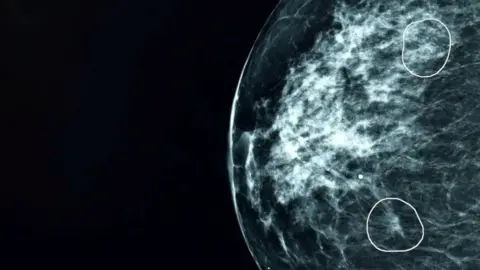

人工智能诊断系统Mia(迈亚)由医疗科技公司凯伦(Kheiron)开发,能够识别常规乳腺X光检查中人眼难以察觉的微小可疑区域。研究结果显示,该系统不仅将癌症检出率提高了10.4%,还显著减轻了医护人员工作负担,加快了检查结果通知速度。

AI辅助诊断实例